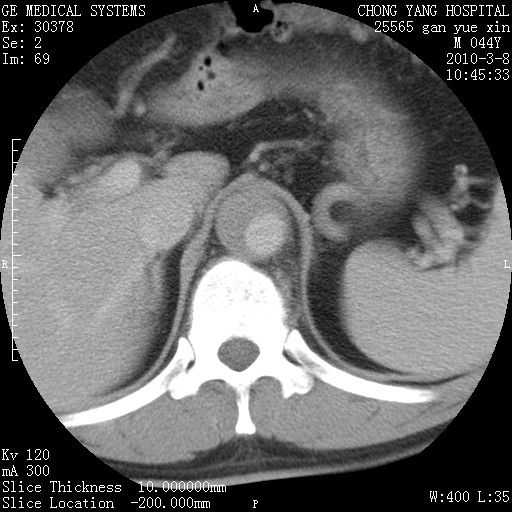

标题: CT24940:主动脉增强,典型病例。 [打印本页]

标题: CT24940:主动脉增强,典型病例。

夹层动脉瘤。

动脉夹层

夹层动脉瘤,典型

主动脉夹层。

动脉夹层的分型:

⒈debakey分型:根据主动脉夹层累及部位,分为三型:ⅰ型:原发破口位于升主动脉或主动脉弓部,夹层累及升主动脉、主动脉弓部、胸主动脉、腹主动脉大部或全部,少数可累及髂动脉。ⅱ型:原发破口位于升主动脉,夹层累及升主动脉,少数可累及部分主动脉弓。ⅲ型:原发破口位于左锁骨下动脉开口远端,根据夹层累及范围又分为ⅲa,ⅲb。ⅲa型:夹层累及胸主动脉。ⅲb型:夹层累及升主动脉、腹主动脉大部或全部。少数可累及髂动脉。

⒉stanford分型:a型:夹层累及升主动脉,无论远端范围如何。b型:夹层累及左锁骨下动脉开口以远的降主动脉。

夹层动脉瘤,少量胸水

夹层动脉瘤;左侧少量胸腔积液。

典型主动脉夹层。